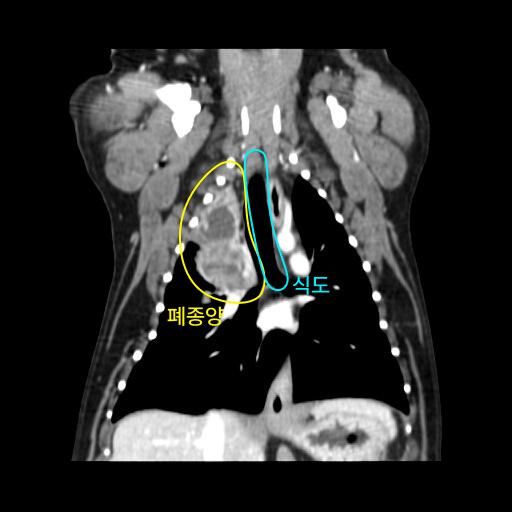

엑스레이 사진과 CT 사진(흉부 앞, 우측 옆)은 첨부하였습니다.

폐 우측 위쪽에 원발성 암이 발생한 것으로 보였습니다.

식도와 심장을 눌러서 기침을 발생시켰습니다.

나쁜 소식은 심장과 혈관이 위치한 안 좋은 부위에 암이 있다는 것이고,

좋은 소식은 심장과 혈관과 아직 붙지 않고 떨어져 있다는 것이었습니다.